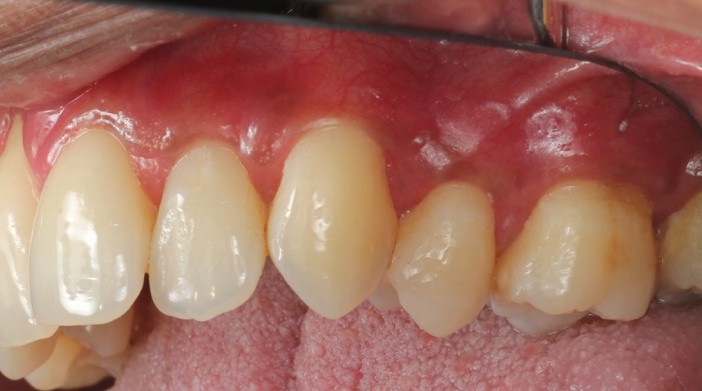

Before and after Periodontal Therapy

![]() | ![]() |

| Untreated severe gum disease | Gum disease treated and stabilised by Dr Halai |